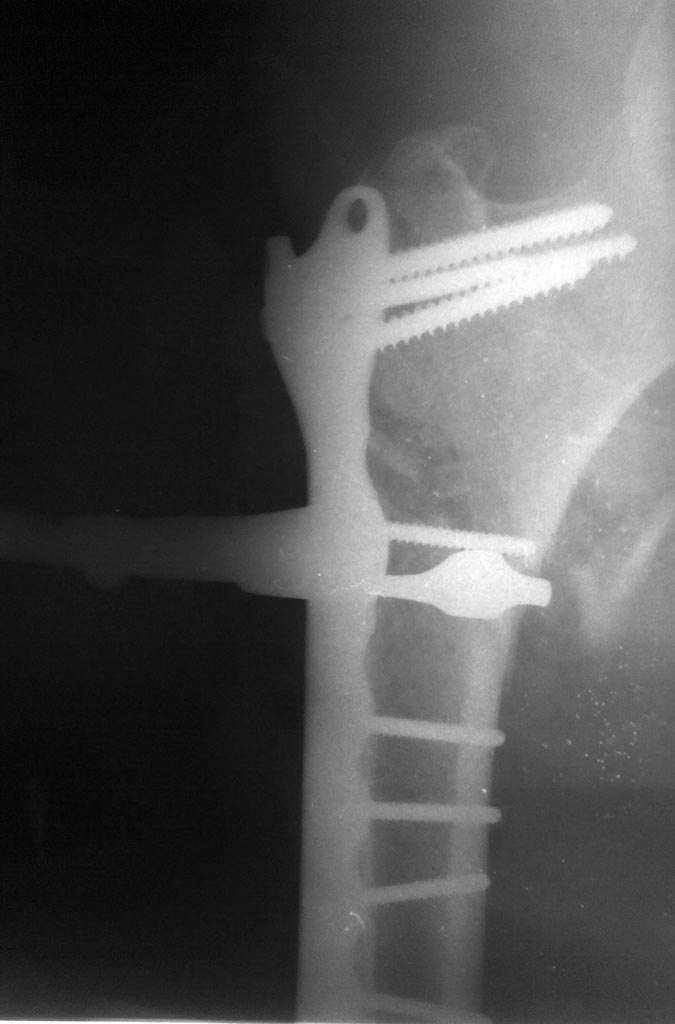

Больной Я.Р 1940 г.р. 08.03.2016 поступил в отд с дс: з/подвертельный

перелом пр.бедренной кости со смещением.

11.03 остеосинтез с пластиной +проволкой.

Имя     : 20160311152054.jpg